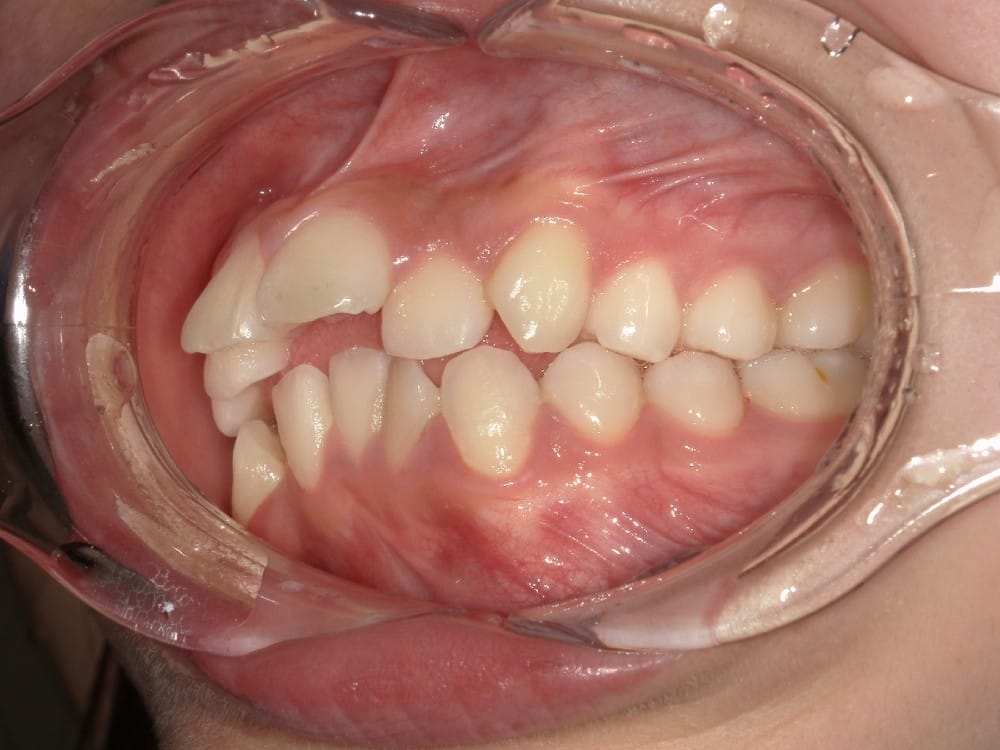

② セファロ(横顔レントゲン)分析

骨格的な問題があるかどうかを数値で評価します。

上顎・下顎の前後関係、前歯の傾斜角度、口元の軟組織のバランスなどを客観的に確認することで、「歯が原因なのか」「骨格が原因なのか」を明確にします。

こうしたケースでは、抜歯によってスペースを確保し、前歯を後方へ移動させることで、口元の印象が大きく改善する可能性があります。

before

after

前歯を数ミリ後退させるだけでも、唇の位置は明確に変わります。

横顔ではEラインとの距離が縮まり、「横顔がすっきりした」「口が自然に閉じられるようになった」と感じられる方が多いです。